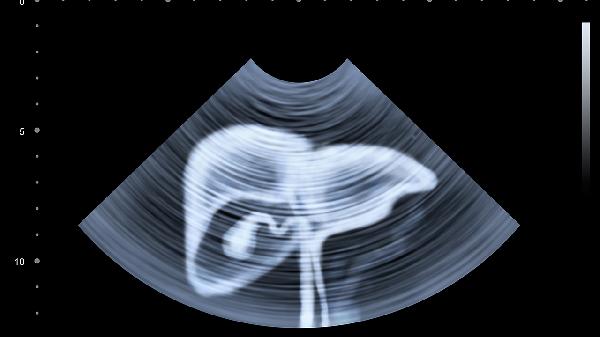

丙肝患者應(yīng)建立規(guī)律的作息習(xí)慣,避免熬夜和過(guò)度勞累,保證每日充足睡眠。飲食方面選擇易消化的高蛋白食物如魚(yú)肉、雞肉和豆制品,適量攝入新鮮蔬菜水果補(bǔ)充維生素。完全戒除飲酒習(xí)慣,避免使用對(duì)肝臟有損傷的藥物。定期復(fù)查肝功能、丙肝病毒RNA和肝臟超聲,監(jiān)測(cè)病情變化。適當(dāng)進(jìn)行散步、太極拳等低強(qiáng)度運(yùn)動(dòng),增強(qiáng)機(jī)體抵抗力。保持樂(lè)觀心態(tài),積極配合醫(yī)生治療,有助于控制疾病進(jìn)展。